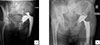

The acetabular defect could introduce heterogeneity and could influence the dislocation rate [9]. Only patients with Paprosky 1 or 2A were considered because higher Paprosky grades often require additional reconstruction techniques such as bone grafting or reinforcement devices, which can alter implant stability and increase the risk of dislocation. In the period study, 489 THA with DMC Novae-E TH were performed (Figures 1 and 2); this DMC was suited for Paprosky 1 or 2A revisions; 220 patients of them were revision arthroplasties. Among these, 40 patients experienced a two-stage revision THA.

Figure 1 Dual-mobility cup Novae-E TH. |

Figure 2 Radiographs (A) and (B) show dislocation and postoperative revision with DMC Novae-E TH, respectively. |